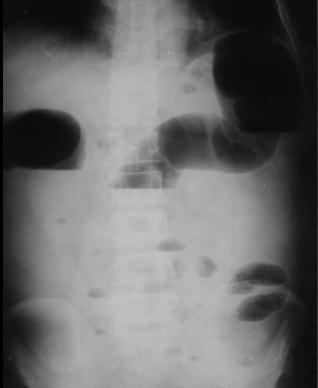

Image hydro-aerique distendue

d'une occlusion du colon . Sa hauteur est souvent

plus que sa largeur et en peripherique de l'abdomen

. |

L'occlusion du colon .

Image hydro-aerique se situe en peripherique du

colon |